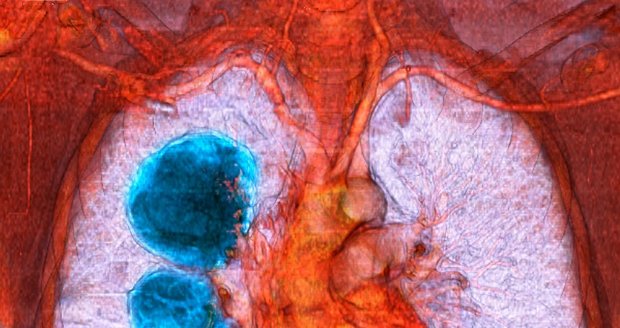

Chronická obstrukční plicní nemoc, neboli CHOPN. Znáte ji, víte, o co jde? Podle Světové zdravotnické organizace patří k nejčastějším příčinám úmrtí na světě. Co je to za nemoc? Koho se týká? Proč na ni lidé umírají? Jak ji předcházet a dá se léčit? Nejen na to v Epicentru odpovídal přednosta Kliniky pneumologie 3. LF UK a Fakultní nemocnice Bulovka, docent Norbert Pauk.

„Chronická obstrukční plicní nemoc je závažné, postupně se zhoršující onemocnění průdušek a plic, které vzniká u pacientů, kteří mají nějaká rizika a současně mají nějakou genetickou vlohu pro to, aby se toto onemocnění rozvíjelo. My přesně nevíme, kdy započne toto onemocnění, ale vlastní projevy, příznaky se objevují ve středním a pozdním věku,“ uvedl v Epicentru docent Pauk s tím, že objevit se ale může i mnohem dříve.

Rozdílem mezi těmito je zvýšená reaktivita průdušek, takže představme si astma, kdy průdušky jsou velmi stažené, kdežto u chronické obstrukční plicní nemoci ta průduška postupně lety tuhne a dochází k jejímu zužování a současně na rozdíl od astmatu může dojít i k postižení plic,“ uvedl Pauk s tím, že rozhodně není radno jakékoli příznaky podceňovat.